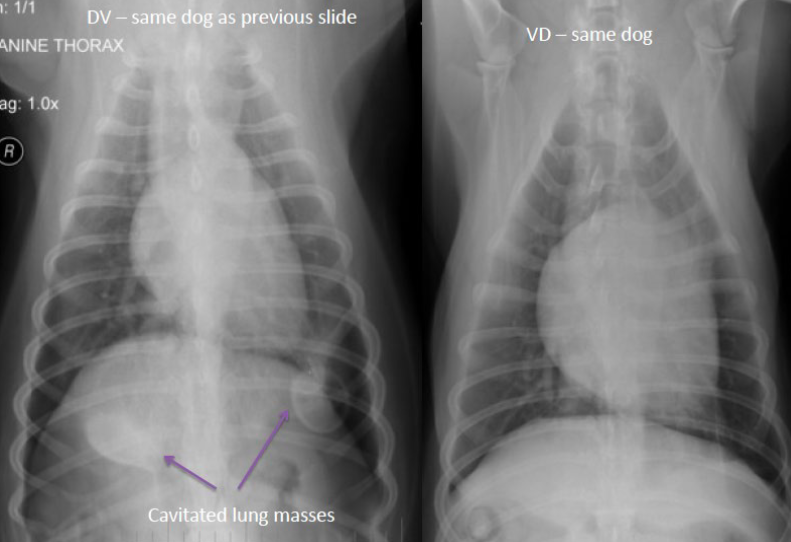

why can you only see the the lung masses in the DV radiograph and not in the VD radiograph?

on the VD, the dorsal lung is against the table and has become (dependent), meaing it’s been squished and is no longer full of air. This makes it appear as soft tissue rather than air, and the soft tissue masses are effeced and do not show up. On the DV, the ventral lung has now become squished and the dorsal lung is airated, making it a different opacity than the lung masses so they appear on the radiograph.